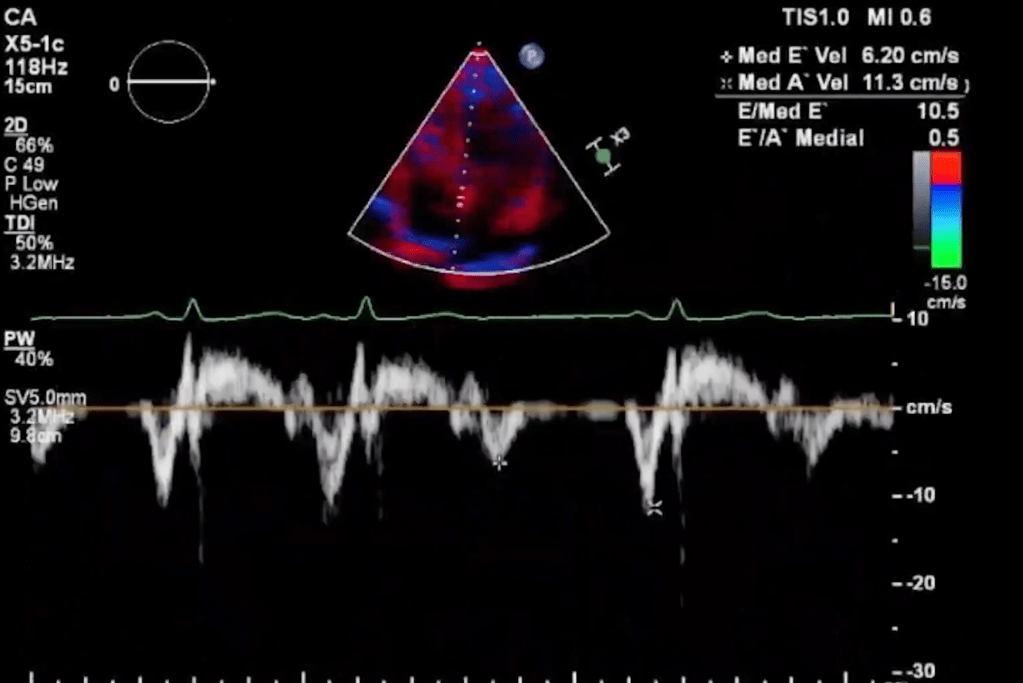

A monitor display of a beating heart sparked the inspiration for HEART Part 1. The medical image of a pulsing image of a heart greeted the audience at the beginning of the piece, projected large over the poised dancers. The 6 performers begin with disjointed machinations and wordless vocalizations, which eventually lead into arcing and circling pathways, pulling each dancer into orbit as they interacted. The dance distinguishes the individual dancers through personalized shapes and gestures while also wrapping them together with the use of mutual partnerships, lifts, and supports. This connection continued to unfold as the dancers evoked the ebbing and flow of the pulsing heart while bleeding into different groupings.